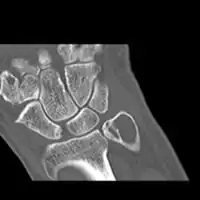

X-ray and CT scan show lytic expansion lesions with clear borders.[1] Expansion of cortex gives the lesion a balloon-like appearance. Larger lesions may appear septated.[10] MRI reveals fluid levels.[1] Bone scan shows outer radiotracer uptake, with a central dark area.[1]

CT scan: ABC ulna near wrist -